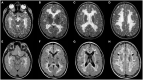

Macrocephaly affects up to 5% of the pediatric population and is defined as an abnormally large head with an occipitofrontal circumference (OFC) >2 standard deviations (SD) above the mean for a given age and sex. Taking into account that about 2-3% of the healthy population has an OFC between 2 and 3 SD, macrocephaly is considered as "clinically relevant" when OFC is above 3 SD. This implies the urgent need for a diagnostic workflow to use in the clinical setting to dissect the several causes of increased OFC, from the benign form of familial macrocephaly and the Benign enlargement of subarachnoid spaces (BESS) to many pathological conditions, including genetic disorders. Moreover, macrocephaly should be differentiated by megalencephaly (MEG), which refers exclusively to brain overgrowth, exceeding twice the SD (3SD-"clinically relevant" megalencephaly). While macrocephaly can be isolated and benign or may be the first indication of an underlying congenital, genetic, or acquired disorder, megalencephaly is most likely due to a genetic cause. Apart from the head size evaluation, a detailed family and personal history, neuroimaging, and a careful clinical evaluation are crucial to reach the correct diagnosis. In this review, we seek to underline the clinical aspects of macrocephaly and megalencephaly, emphasizing the main differential diagnosis with a major focus on common genetic disorders. We thus provide a clinico-radiological algorithm to guide pediatricians in the assessment of children with macrocephaly.